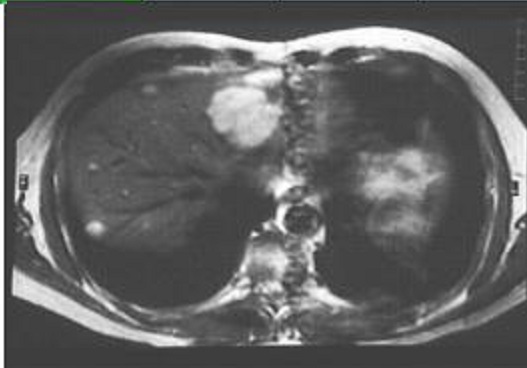

Image ỈRM

ponderee T2 coupe axiale

du foie : Aspect hyperintense d'une hemagiome du foie

, lobe droit |

Aspect enorme dilatation des

voies biliaires et image de dilatation du canale de

Wirsung : Tumeur de la tete du pancreas . Image

cholangio-IRM du foie